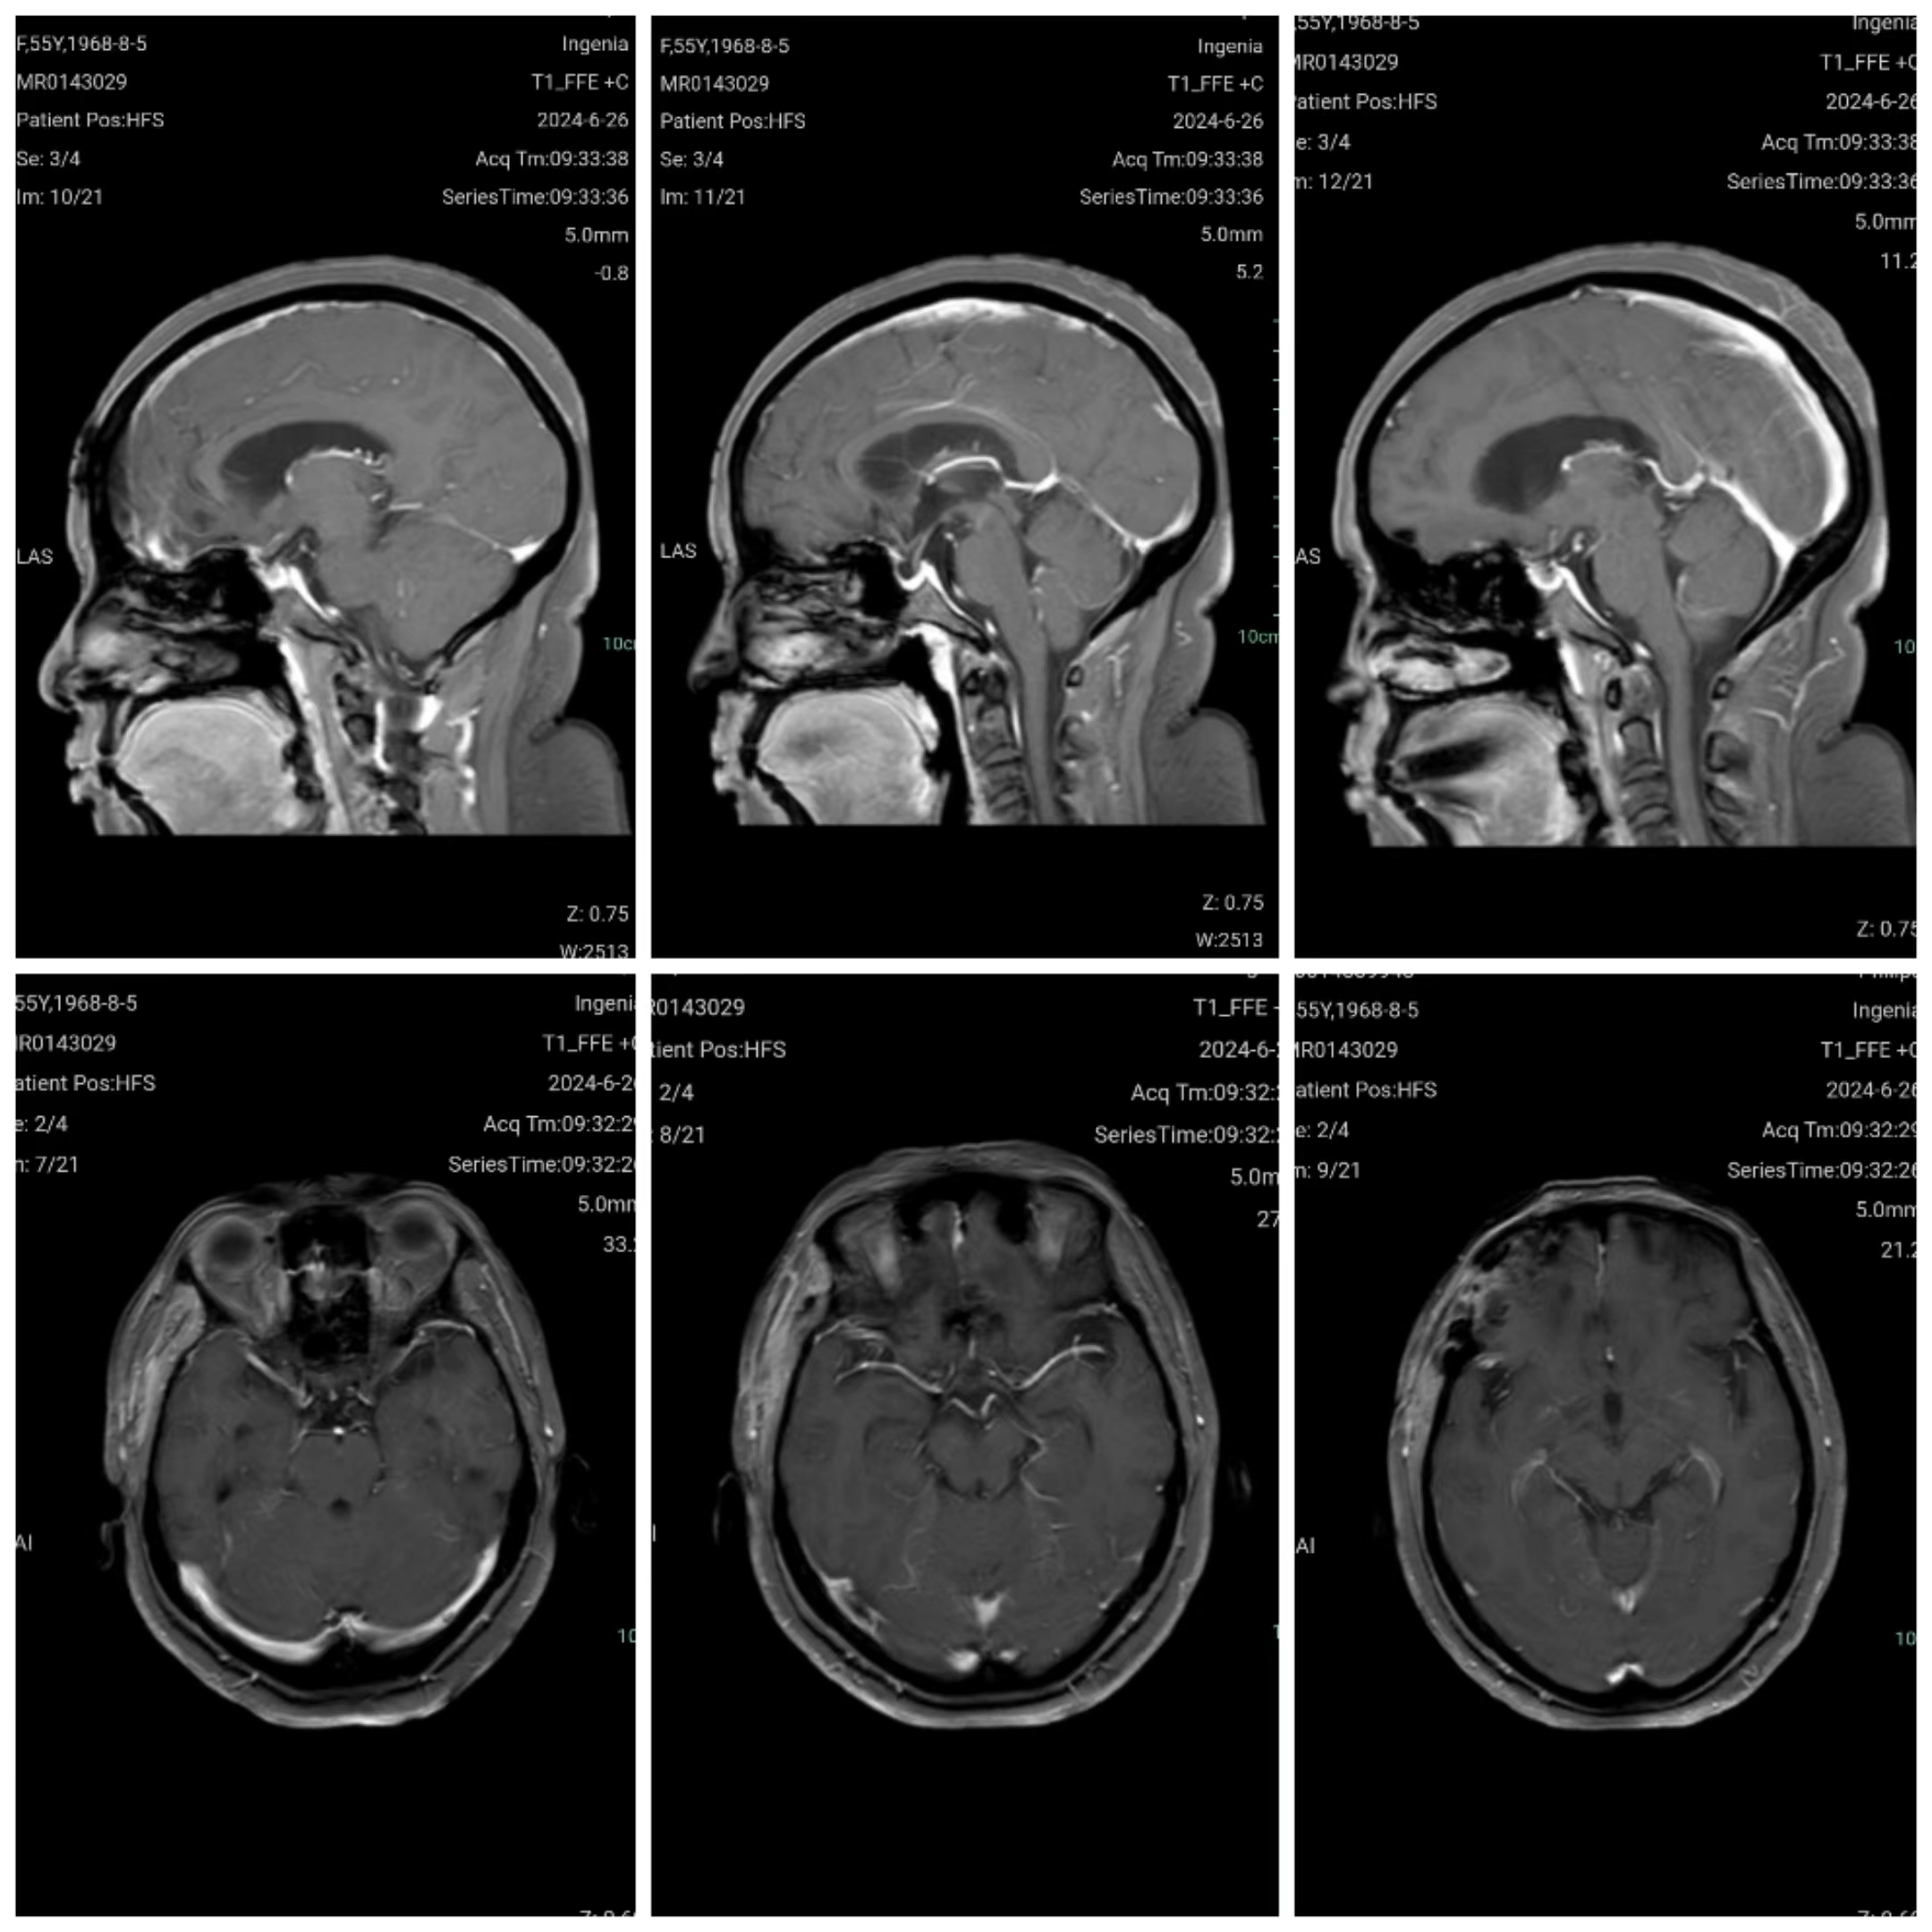

颅脑磁共振增强扫描示前颅底巨大脑膜瘤,基底前至鸡冠,后达垂体窝,基底宽。

手术前与手术后第十天后颅脑增强磁共振比较:前颅底巨大脑膜瘤影像学切除完全。

术后三个月颅脑强化磁共振显示肿瘤无明显残留。